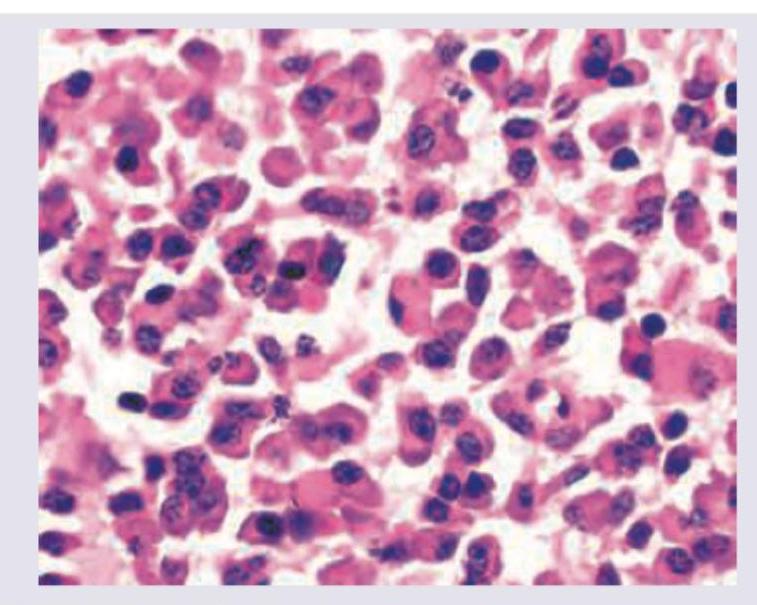

Identify the intracellular hyaline body.

Explanation: ***Russell bodies*** - The image depicts **plasma cells** containing large, eosinophilic, and homogenous cytoplasmic inclusions, which are characteristic features of **Russell bodies**. - These bodies represent an accumulation of **excess immunoglobulins** within the dilated cisternae of the endoplasmic reticulum in plasma cells [1]. *Corpora amylacea* - These are small, concentrically layered, usually **basophilic bodies** found extracellularly in the prostate, brain, and lung. - They are composed of glycoproteins and often increase with age, not directly seen here as intracellular hyaline bodies in plasma cells. *Hyaline droplets* - These are typically **intracellular protein reabsorption droplets** found in epithelial cells, particularly renal tubular cells, when there is excessive proteinuria [1]. - They are generally smaller and more uniformly distributed compared to Russell bodies and are not pathognomonic for plasma cells. *Mallory Hyaline bodies* - Also known as Mallory bodies, these are **eosinophilic, rope-like cytoplasmic inclusions** found in the hepatocytes of patients with alcoholic liver disease or certain other liver conditions [1]. - They are composed of intermediate filaments and are distinct from the immunoglobulin inclusions seen in plasma cells. **References:** [1] Kumar V, Abbas AK, et al.. Robbins and Cotran Pathologic Basis of Disease. 9th ed. Cellular Responses to Stress and Toxic Insults: Adaptation, Injury, and Death, pp. 73-74.